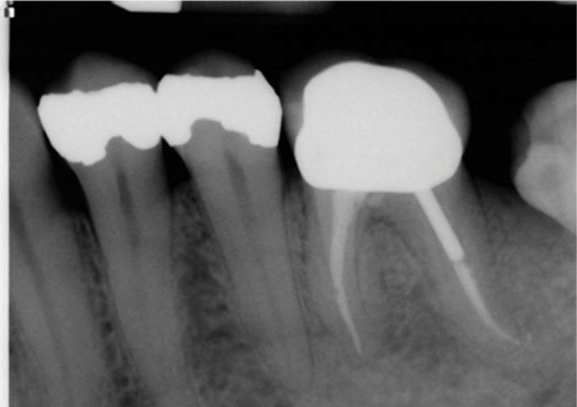

(5.) Preoperative radiograph of tooth No. 19 following a pulpectomy procedure that was complicated by an intraoperative furcal perforation.

Figure 5

(6.) Postoperative radiograph showing immediate perforation repair using MTA followed by complete obturation.

Figure 6

(7.) One-year follow-up periapical and bitewing radiographs demonstrating the absence of apical pathosis or furcal pathosis at the site of

the perforation.

Figure 7

(8.) One-year follow-up periapical and bitewing radiographs demonstrating the absence of apical pathosis or furcal pathosis at the site of

Figure 8